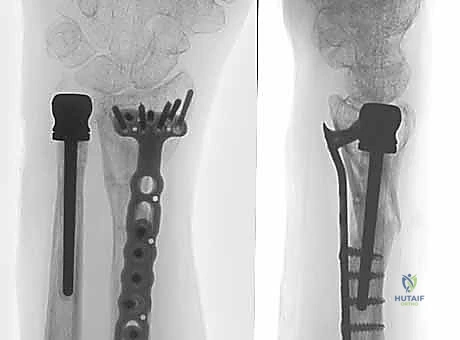

5. زراعة المفصل النهائي

بعد تحديد الحجم المثالي، يتم إدخال المفصل الصناعي النهائي. تتكون معظم المفاصل الحديثة من جذع معدني (غالبًا من التيتانيوم) ورأس أملس (قد يكون معدنيًا أو من السيراميك أو البايروكربون). يتم تثبيت الجذع داخل العظم إما بالضغط (Press-fit) أو باستخدام الأسمنت العظمي، حسب جودة عظام المريض.

6. إعادة بناء الأنسجة الرخوة (الخطوة الأهم للاستقرار)

ما يميز الجراح الخبير هو كيفية تعامله مع الأنسجة الرخوة. يقوم الأستاذ الدكتور محمد هطيف بخياطة وإعادة ربط كبسولة المفصل ومجمع الغضروف الليفي الثلاثي (TFCC) حول المفصل الصناعي الجديد. يتم تمرير خيوط قوية عبر ثقوب مخصصة في المفصل الصناعي لضمان تثبيت الأربطة بشكل محكم، مما يمنع خلع المفصل مستقبلاً.